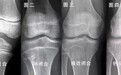

骨骺板的骨化完成与否决定了一个人还有没有长高的空间。如何判断骺板有没有骨化完成?首先就要去看骨骺线有没有闭合,一般成年人的骨骺线都已完全闭合,这也是为什么当人长到一定的阶段,就不会再继续长高的原因了。所以在骨骺线没有闭合的这段区间内,是孩子长高的“黄金阶段”,许多家长怕错过孩子的“黄金阶段”就会因过度焦虑而选择一些有创的办法。